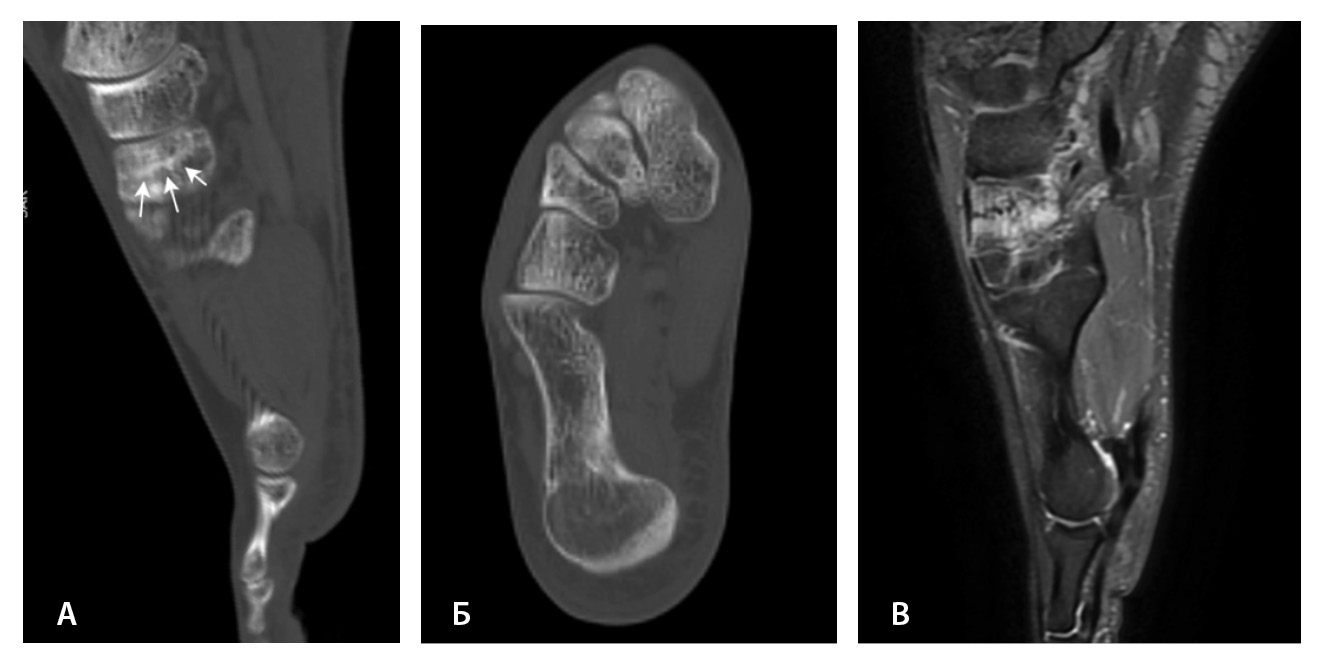

Рис. 3. Рентгеннегативный перелом ладьевидной кости: А – Т2-взвешенное изображение, аксиальная плоскость; Б – PD-FS-взвешенное изображение, аксиальная плоскость (стрелками указана линия перелома); В – рентгенография (кругом отмечена область перелома)

МРТ – первоначальный метод диагностики при подозрении на стрессовые переломы, так как ранним признаком таких переломов служит отек костного мозга пораженной кости, ярко выделяющийся среди остальных неизмененных костей. Отсутствие визуализации костного мозга затрудняет диагностику такого рода повреждений при рентгенографии и КТ (рис. 4). Чувствительность МРТ в выявлении стресс-переломов достигает 99% (95–100%), а специфичность – 97% (88–100%). Несмотря на то что исторически сцинтиграфия была основным методом обнаружения стресс-переломов с почти 100% чувствительностью, в настоящее время выполнение радионуклидного метода не рекомендуется из-за его низкой специфичности и высокой дозы ионизирующего излучения [54].

Рис. 4. Стресс-перелом промежуточной клиновидной кости: А – компьютерная томография (КТ), сагиттальная плоскость; Б – КТ, аксиальная плоскость; В – импульсная последовательность STIR, сагиттальная плоскость. Линия стресс-перелома слабо видна на КТ-изображениях, обнаруживается только при сагиттальных КТ-реконструкциях (стрелки). На изображениях магнитно-резонансной томографии отек костного мозга промежуточной клиновидной кости в режиме STIR ярко выделяется среди неизмененных костей